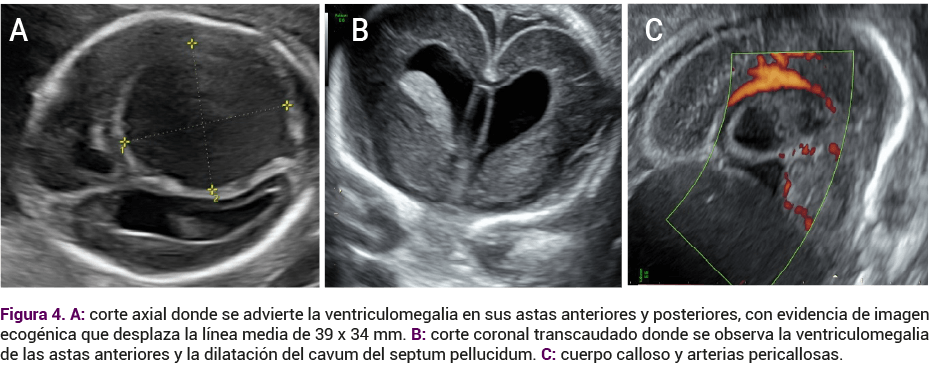

El seguimiento institucional se llevó a cabo con una neurosonografía fetal avanzada practicada a las 21 semanas de gestación y que reportó dilatación del septo de la faringe, cuerpo calloso y arterias pericallosas (Figura 4). Los tálamos se advirtieron de contorno, tamaño y ecogenicidad normales, con dilatación ventricular de las astas posteriores y anteriores (Figura 4 B y C). Los datos del atrio ventricular izquierdo y derecho midieron 16 y 19 mm respectivamente.

<strong>Figura 4</strong>

Figura 4.

Los plexos coroideos eran regulares y simétricos, desplazados por la lesión quística occipital derecha supratentorial extraparenquimatosa, de contenido hipoecogénico denso que solo observó captación periférica al Doppler color, de 39 x 34 mm (Figura 5).